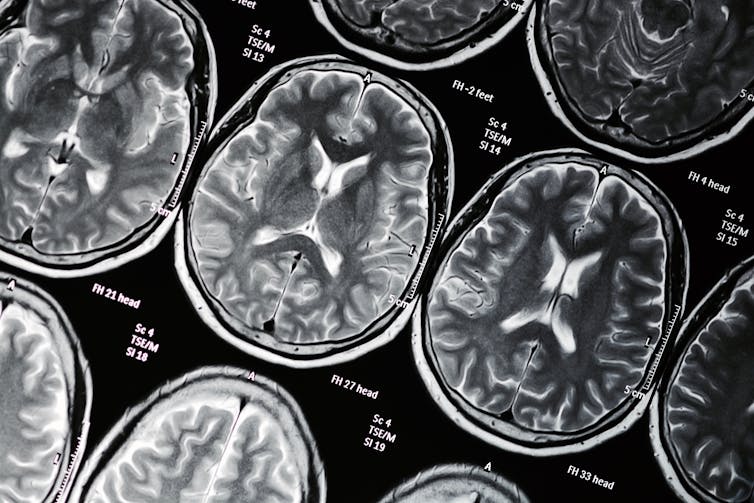

Tapi bagaimana menggunakan obat mempengaruhi pikiran? Dalam tiga penelitian terbaru, yang diterbitkan dalam The Journal of Psychopharmacology, Neuropsychopharmacology dan International Journal of Neuropsychopharmacology, kami menunjukkan bahwa ganja bisa mempengaruhi sejumlah proses kognitif dan psikologis.

Tetrahydrocannabinol (THC) adalah senyawa psikoaktif utama dalam ganja. Hal ini bekerja pada “sistem endocannabinoid” otak, yang merupakan reseptor yang merespons komponen kimia ganja. Reseptor ganja berpenduduk padat di area prefrontal dan limbik di otak, yang berkaitan dengan emosi yang muncul dalam motivasi dan rasa dihargai. Mereka mengatur bagaimana zat kimia otak dopamin, asam gamma-aminobutirat (GABA), dan glutamat memberi sinyal.

Dalam penelitian kami, kami menguji kognisi 39 orang dengan gangguan tersebut (yang (kami minta mereka bersih dari ganja pada hari pengujian), dan membandingkannya dengan 20 orang yang tidak pernah atau jarang menggunakan ganja. Kami menunjukkan bahwa peserta dengan kondisi tersebut memiliki kinerja yang jauh lebih buruk pada tes memori dari Cambridge Neuropsychological Test Automated Battery (CANTAB) dibandingkan dengan pengguna terkontrol, yang tidak pernah atau sangat jarang ganja yang digunakan. Ini juga berdampak negatif pada “fungsi eksekutif” mereka, yang merupakan proses mental termasuk pemikiran yang fleksibel. Efek ini tampaknya terkait dengan usia di mana orang mulai menggunakan obat – semakin muda mereka, semakin terganggu fungsi eksekutif mereka.

Dalam penelitian terbaru kami, kami menggunakan tugas pencitraan otak, di mana peserta ditempatkan di pemindai dan melihat kotak oranye atau biru. Kotak oranye akan menghasilkan hadiah uang, setelah beberapa saat, jika peserta memberikan tanggapan. Pengaturan ini membantu kami menyelidiki bagaimana otak merespons penghargaan. Kami fokus terutama pada striatum ventral, yang merupakan wilayah kunci dalam sistem penghargaan otak. Kami menemukan bahwa efek pada sistem penghargaan di otak tidak kentara, tanpa efek langsung ganja di ventral striatum. Namun, peserta dalam penelitian kami adalah pengguna ganja moderat. Efeknya mungkin lebih terasa pada pengguna ganja dengan penggunaan yang lebih parah dan kronis, seperti yang terlihat pada orang yang mengalami gangguan penggunaan ganja.

Studi lain terhadap 780 remaja menunjukkan bahwa hubungan antara penggunaan ganja dan pengalaman psikotik juga terkait dengan wilayah otak yang disebut “uncus”. Ini terletak di dalam parahippocampus (terlibat dalam memori) dan olfactory bulb) (terlibat dalam pemrosesan bau), dan memiliki sejumlah besar reseptor cannabinoid. Ini juga sebelumnya telah dikaitkan dengan skizofrenia dan pengalaman psikotik.